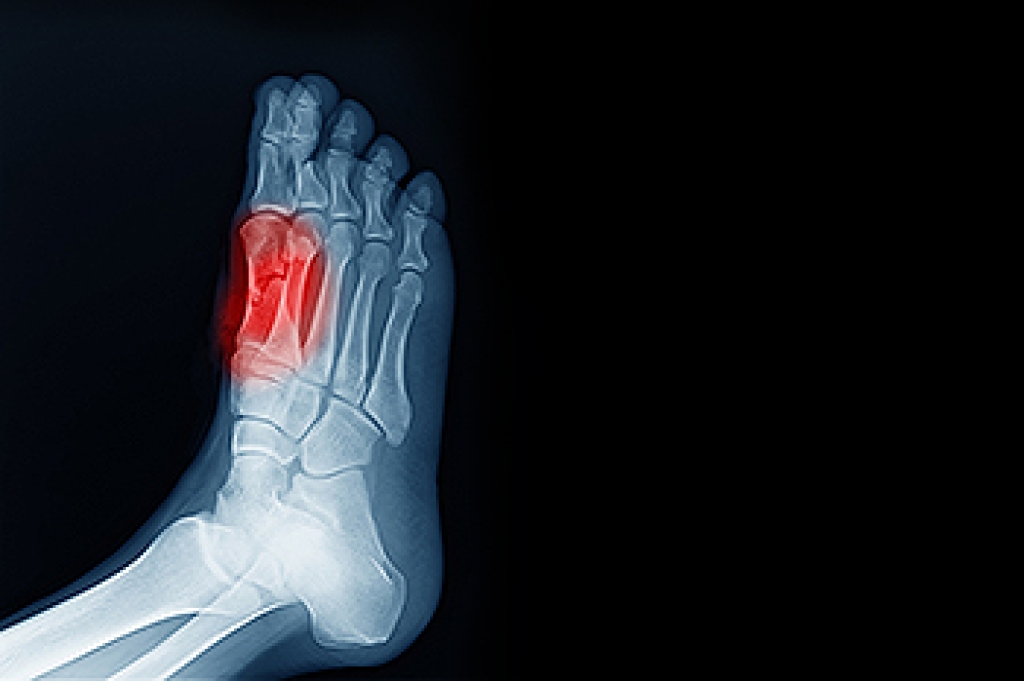

Toe Pain May Be Caused by Sesamoiditis

The sesamoid bones of the feet are small yet significant structures embedded within tendons under the big toe. They play a vital role in joint stabilization and the ability to raise the toe. Sesamoiditis usually results from post-traumatic or degenerative causes, causing localized pain and swelling, with tenderness over the affected bones. Factors contributing to sesamoiditis include osteoarthritis, foot deformities, and high-impact activities. Other potential causes of sesamoiditis include wearing high heels, increased body weight, running on the forefoot, and a larger size of sesamoids. Treatment may include footwear modifications and orthotic shoe inserts. In severe cases, steroid injections or surgery may be necessary to alleviate symptoms and prevent further complications. Seeking a prompt evaluation by a podiatrist is essential. If you are experiencing persistent toe pain or suspect sesamoiditis, it is suggested that you schedule an appointment with a podiatrist for an exam, a diagnosis, and appropriate treatment options.

Sesamoiditis is an unpleasant foot condition characterized by pain in the balls of the feet. If you think you’re struggling with sesamoiditis, contact Charles Oehrlein, DPM of Hoover Foot Care. Our practitioner will treat your condition thoroughly and effectively.

Sesamoiditis

Sesamoiditis is a condition of the foot that affects the ball of the foot. It is more common in younger people than it is in older people. It can also occur with people who have begun a new exercise program, since their bodies are adjusting to the new physical regimen. Pain may also be caused by the inflammation of tendons surrounding the bones. It is important to seek treatment in its early stages because if you ignore the pain, this condition can lead to more serious problems such as severe irritation and bone fractures.

Causes of Sesamoiditis

- Sudden increase in activity

- Increase in physically strenuous movement without a proper warm up or build up

- Foot structure: those who have smaller, bonier feet or those with a high arch may be more susceptible

Treatment for sesamoiditis is non-invasive and simple. Doctors may recommend a strict rest period where the patient forgoes most physical activity. This will help give the patient time to heal their feet through limited activity. For serious cases, it is best to speak with your doctor to determine a treatment option that will help your specific needs.